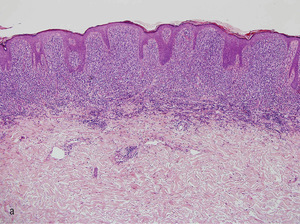

Rycina 2. (a) Badanie histopatologiczne blaszki charakterystycznej dla ziarniniaka grzybiastego ukazuje gęsty naciek komórek jednojądrzastych w obrębie górnej warstwy skóry właściwej. (b) Badanie histopatologiczne guza w przebiegu ziarniniaka grzybiastego ukazuje znaczny i rozległy naciek komórek jednojądrzastych bez cech epidermotropizmu. (c) Analiza polimorfizmu konformacji jednoniciowych fragmentów DNA. Na żelu poliakrylamidowym stwierdzono obecność klonu limfocytów T w obrębie skóry i poliklonalność krwi obwodowej.

– badania histopatologicznego (ryc. 2a i 2b)